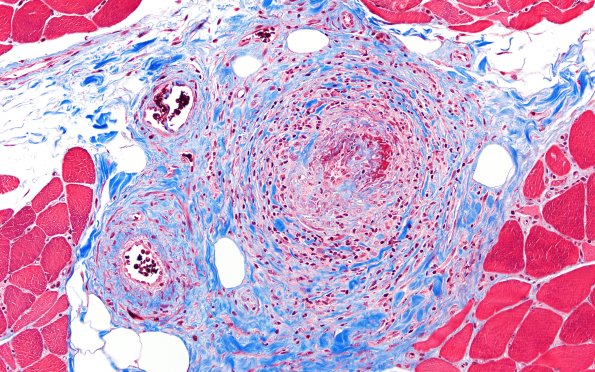

Washington University Experience | PERIPHERAL NEUROPATHY | 11 VASCULITIS - VASCULOPATHY | 3 Vasculitis - NOS | 31F3 Vasculitis (Case 31) TRI 20X

Trichrome staining shows the collagen deposition resulting in focal scarring of the vessel walls and stains the fibrin deposition. (Trichrome)